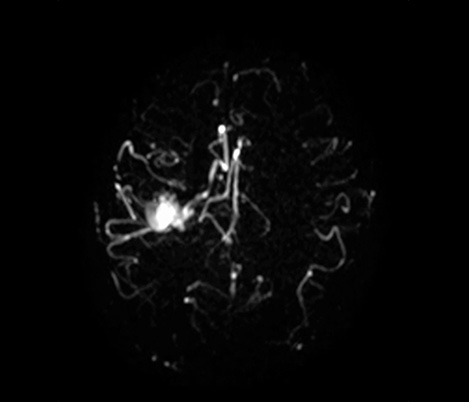

Dr Tetsuya Yoneda, Kumamoto University - Japan talks about his collaboration with Philips on a technique called SWIp developed for susceptibility weighted imaging.

...to clinical practice

Dr Chip Truwit, Hennepin County Medical Center - Minneapolis - USA explains how SWIp became an integral part of all MR trauma scans.